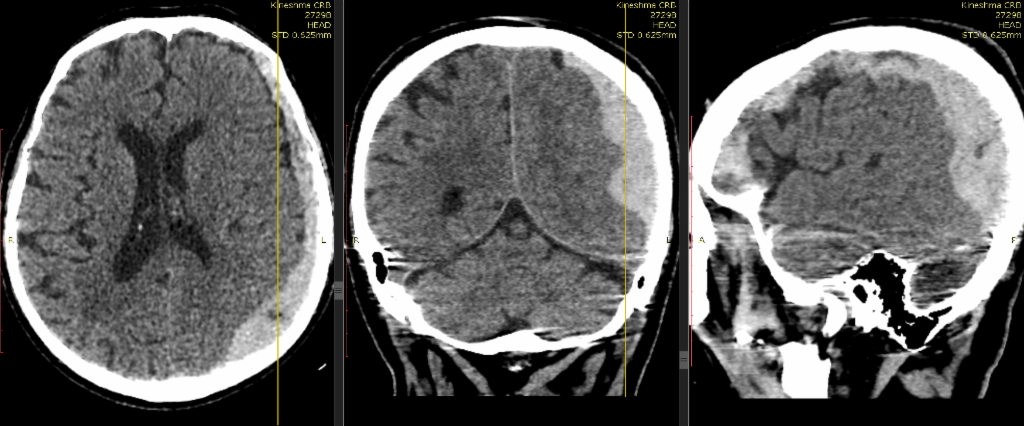

Инсульт удаление гематомы